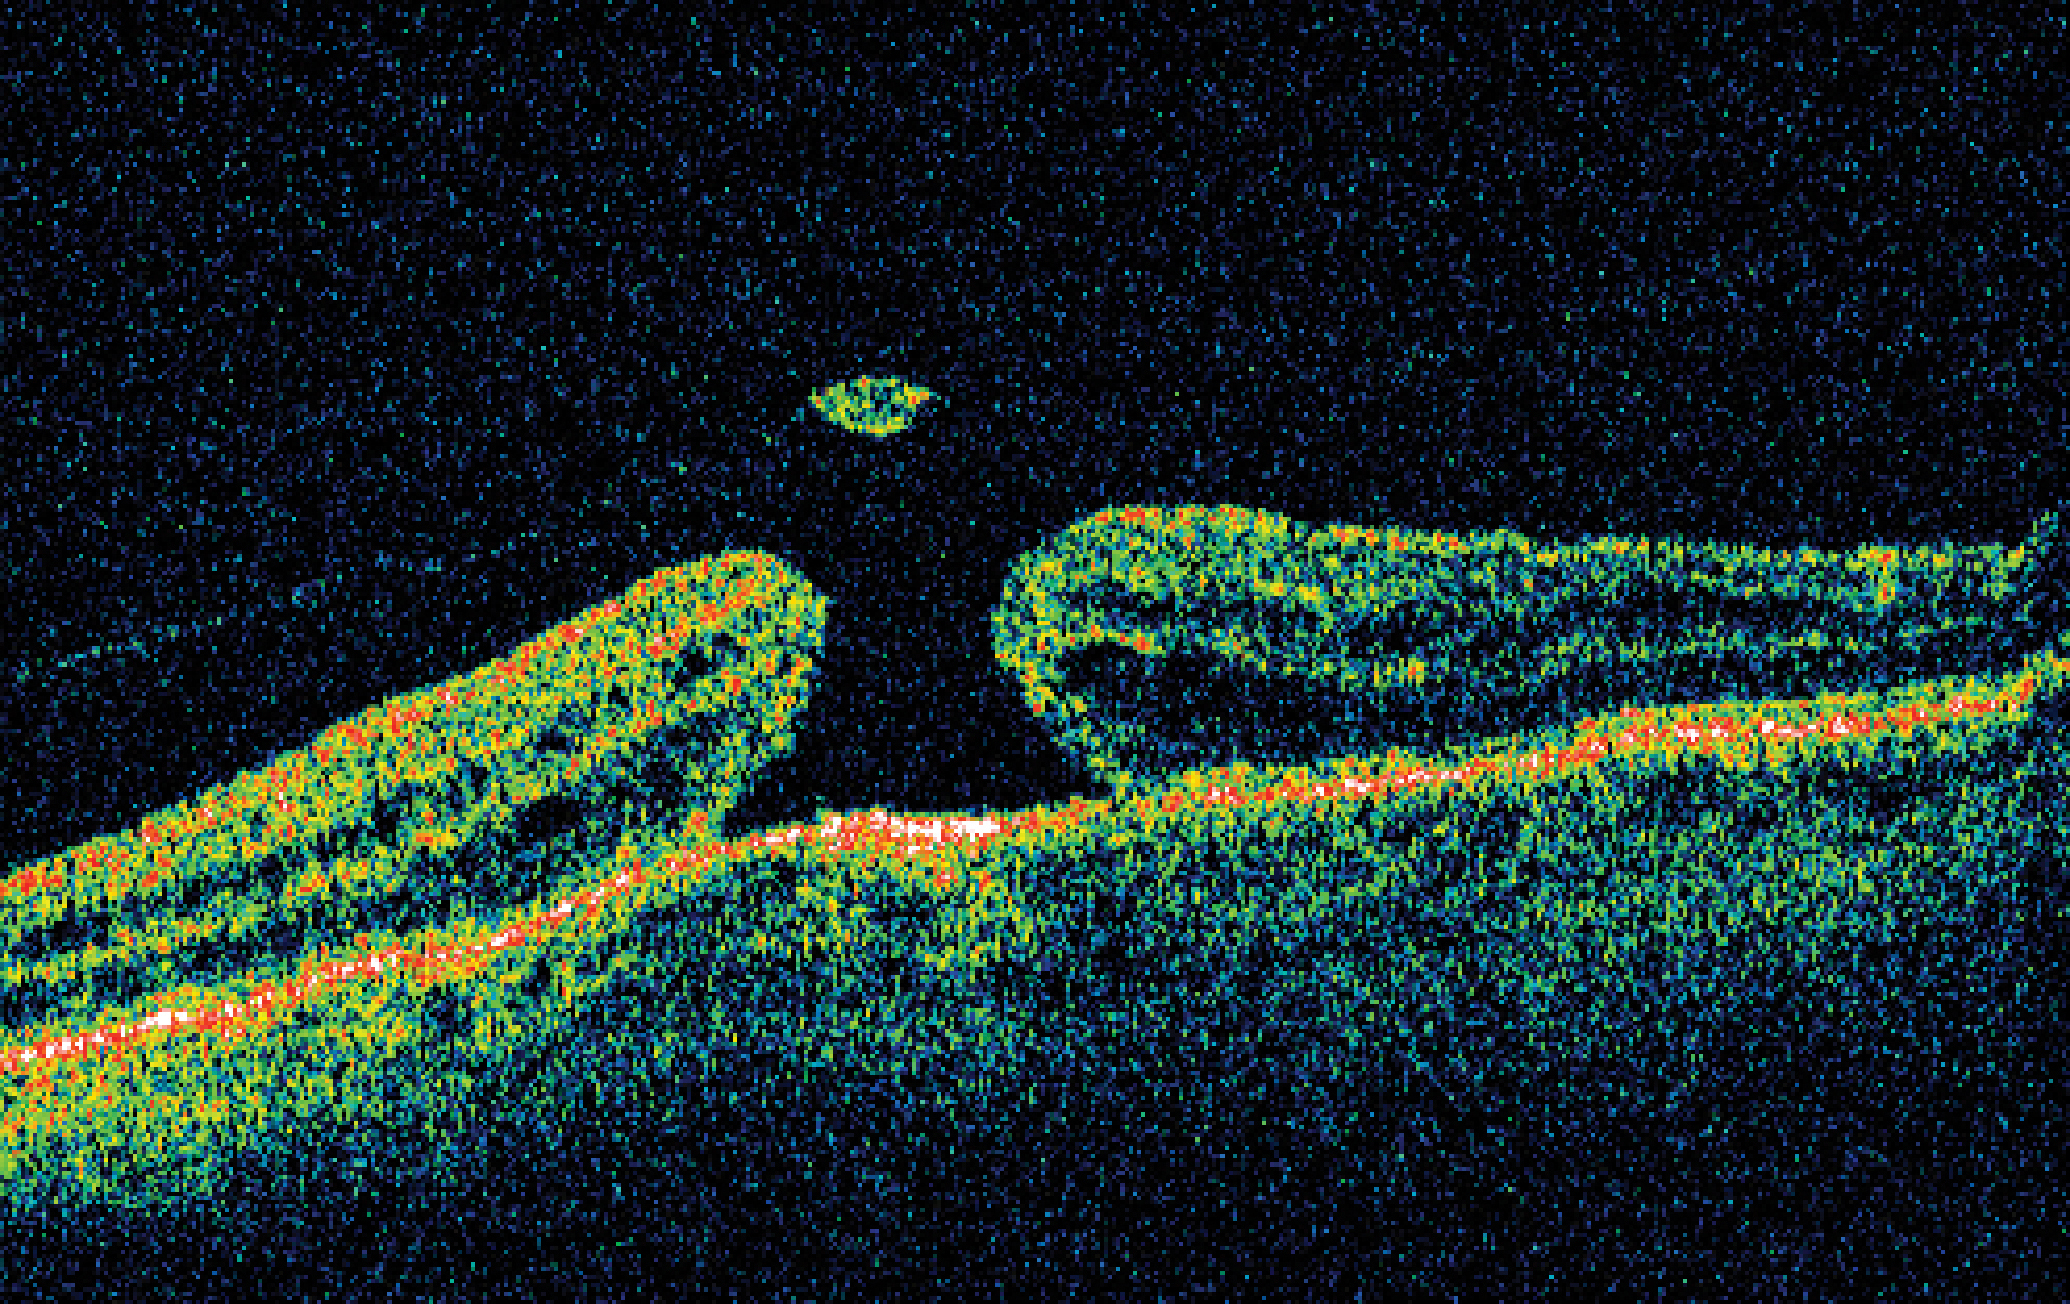

Для демонстрации результатов представляем клинический случай идиопатического макулярного разрыва пациентки В., подтвержденного при ОКТ-сканировании (рисунок 2). Результатом проведенного фиксационного теста является верхне-левая локализация предпочтительного ретинального локуса (рисунок 3).

Рисунок 3. Верхне-левая локализация предпочтительного ретинального фокуса пациента В. с идиопатическим макулярным разрывом.

Figure 3. Upper-left localization of the preferred retinal focus of patient B. with an idiopathic macular hole.

Таким образом, мы видим, что предпочтительный ретинальный локус располагается по краю макулярного разрыва в верхнее-левом секторе сетчатки.